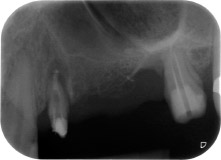

Un mes después, en el día de la intervención, el dolor y la inflamación se habían reducido al mínimo en la pieza 24, pero seguía habiendo una movilidad de clase II de Miller. Después de la apertura de los colgajos y de la limpieza del tejido infectado periapical y perirradicular, la extensión del defecto óseo quedó evidente (figuras 2 y 3).

En la raíz bucal, faltaba todo el hueso vestibular y distal. Básicamente, la fijación se limitó a la raíz palatal, lo que corroboró el mal pronóstico preliminar. La pieza 27 también mostró una fijación horizontal reducida (figura 12) y una rarefacción apical mínima (figura 1), si bien sin síntomas clínicos.